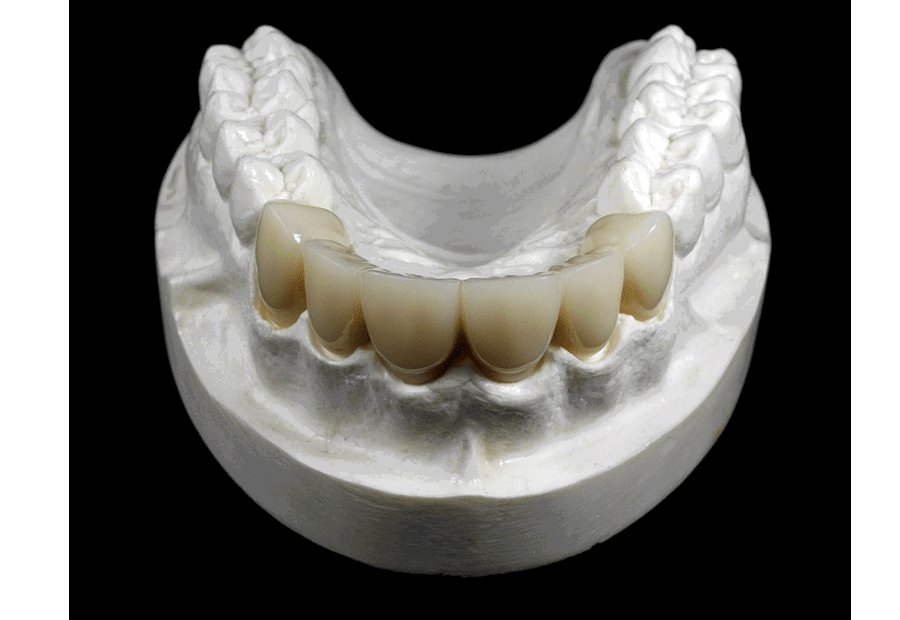

Especialidad odontológica enfocada en la restauración integral de la salud oral devolviéndole al paciente una función masticatoria adecuada y mejorando su estética dental. Es un enfoque completo que puede resolver problemas dentales complejos y mejorar la calidad de vida de los pacientes al resolver pérdidas parciales o totales de dientes, problemas de maloclusión, desgaste dental severo y problemas estéticos como dientes desalineados, descoloridos o malformaciones dentales.

La rehabilitación oral se adapta a las necesidades individuales de cada paciente para proporcionar una solución personalizada y completa a sus problemas dentales brindando calidad de vida a los pacientes a largo plazo. Dentro de los posibles tratamientos a realizar tenemos puentes y coronas libres de metal, prótesis sobre implantes, prótesis parcial removible y totales.